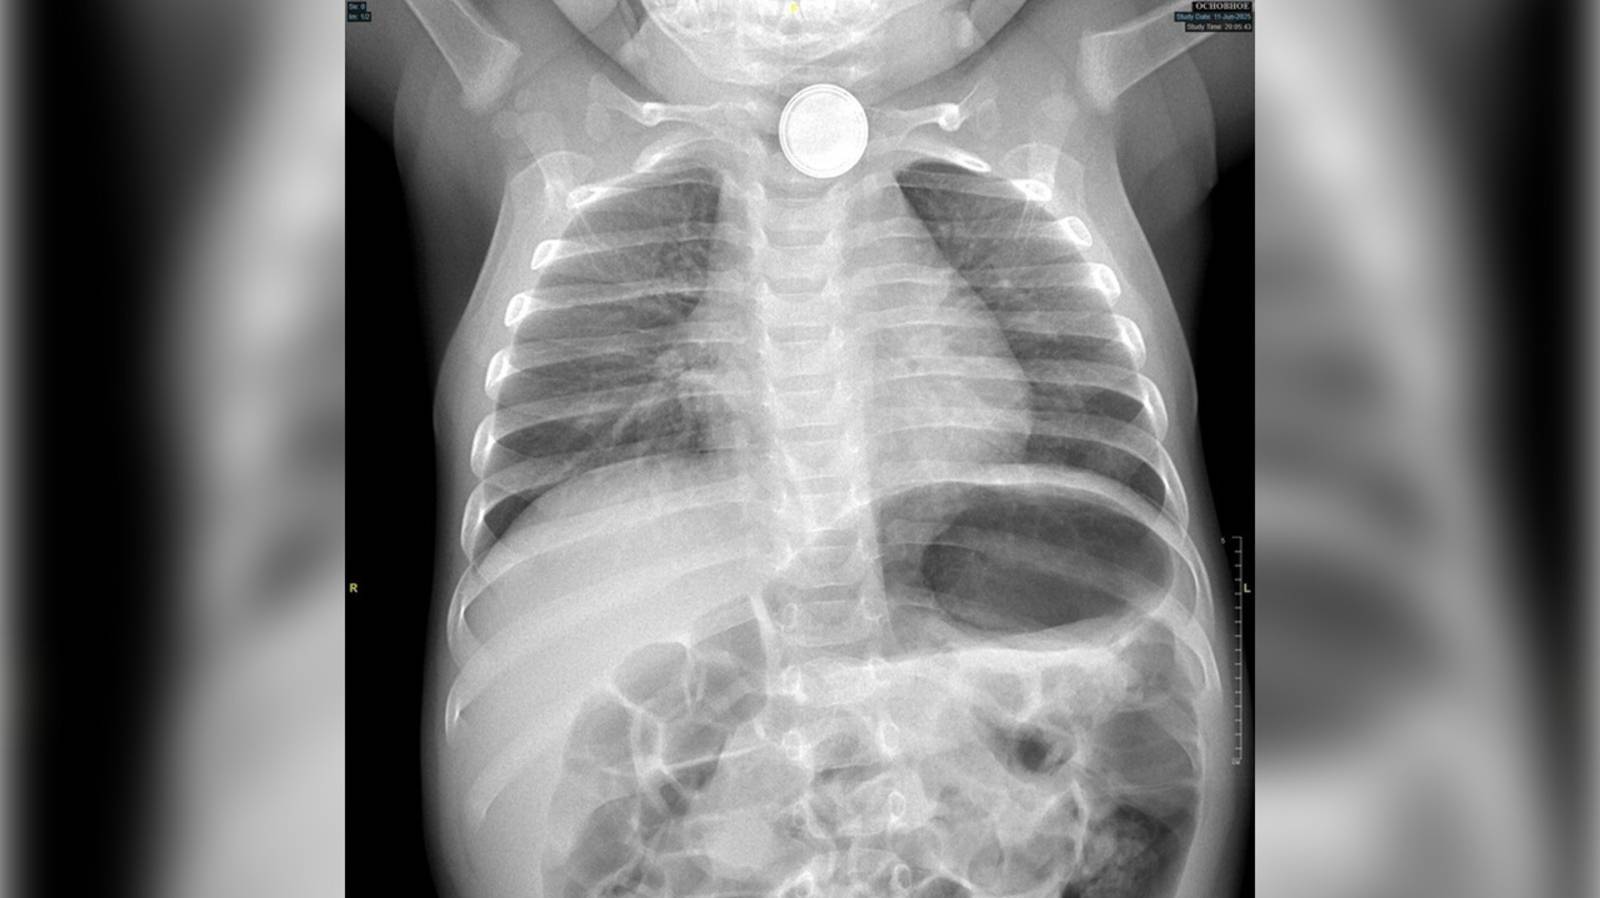

Ребенок съел вату

Ребенок съел вату 105 фото